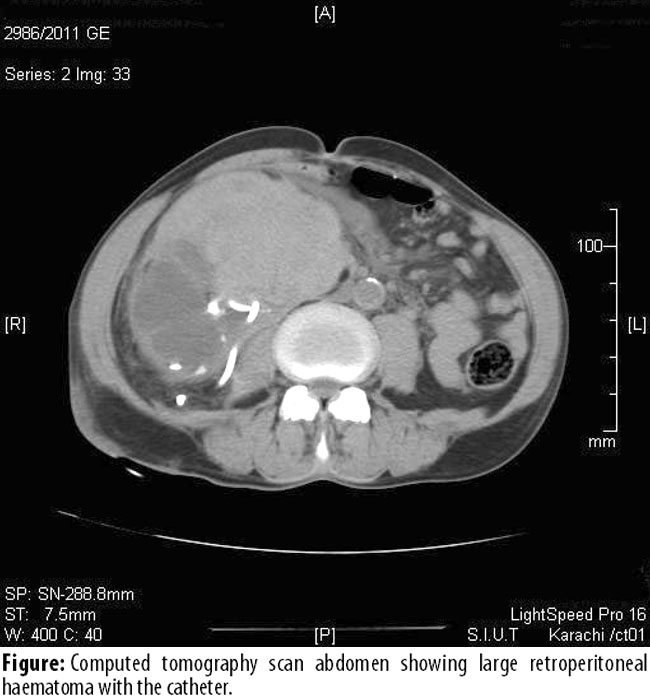

Early complications comprised sepsis 6 (2%), retroperitoneal haematoma 5 (1.6%) (Figure),

haematuria 2 (0.6%), and urinoma 1 (0.3%). Complications such as perforation of adjacent viscera and pneumothorax were not observed.